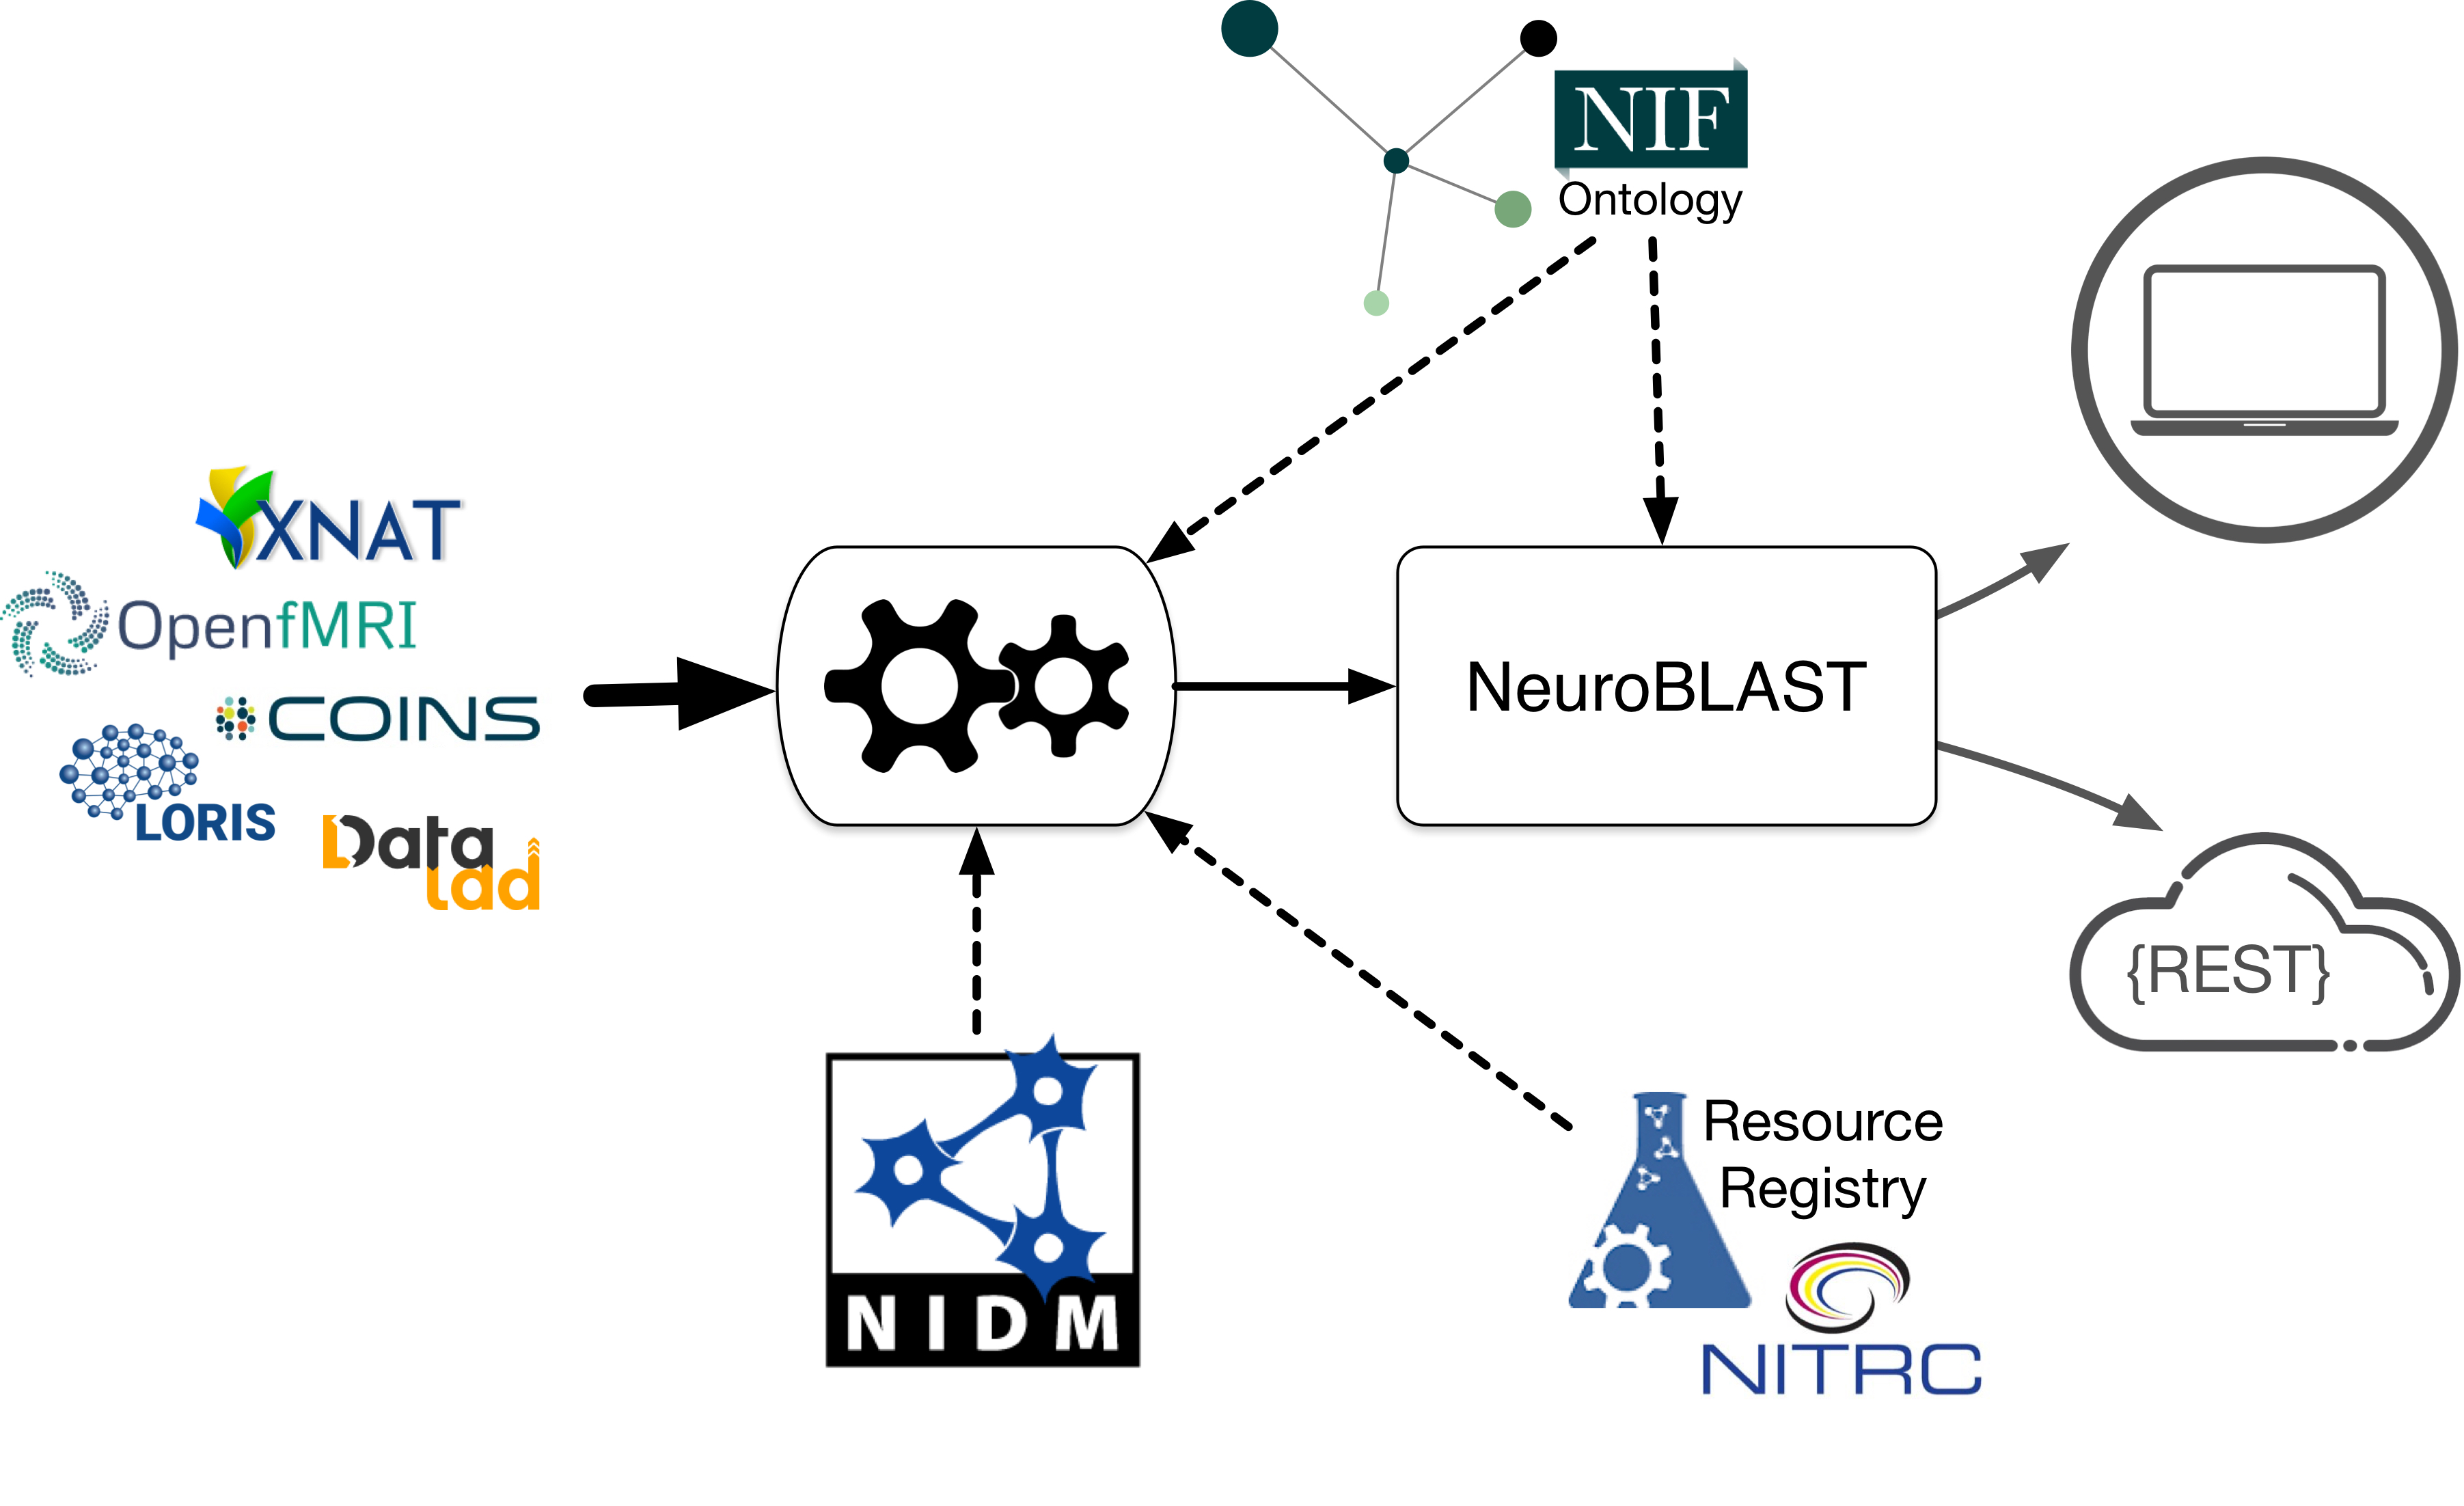

ReproNim is developing an integrated application, NeuroBLAST, that will powerfully enable user-specified search and publish functions to data repositories, published studies, versioned software packages, study-related questions, and content. Included within the NeuroBLAST suite are terminology tools and services that enhance search, data annotation and integration, to help researchers make their data FAIR. We also provide a registry of neuroimaging tools and services to aid researchers in finding the tools they need for their research and to provide information on their use by provision and tracking Research Resource Identifiers (RRIDs).

The NeuroBlast service will allow users to find matching/similar studies based on a combination of task, analysis, and activation patterns. This novel environment will utilize all information about a study enabling researchers to find similar studies utilizing a number of different similarity metrics. This service will employ deep semantics to enhance the search for similar data sets utilizing multiple features for comparison.

- A collection of search and discovery services for neuroimaging data

- A set of related tools to assist researchers in making data FAIR

- Tools to help developers integrate FAIR data into their applications

Neuroimaging Resource Registry

The resource registry provides information on neuroimaging relevant research resources: data, information, and software. The registry works with domain providers, such as NITRC, to provide unique Research Resource Identifiers to enable resource citation and tracking in the literature. The registry provides services for resource owners to track who is using their resources. Through our research resource reports, researchers can discover useful tools, see who is using them, be alerted to any known issues and find other related tools.